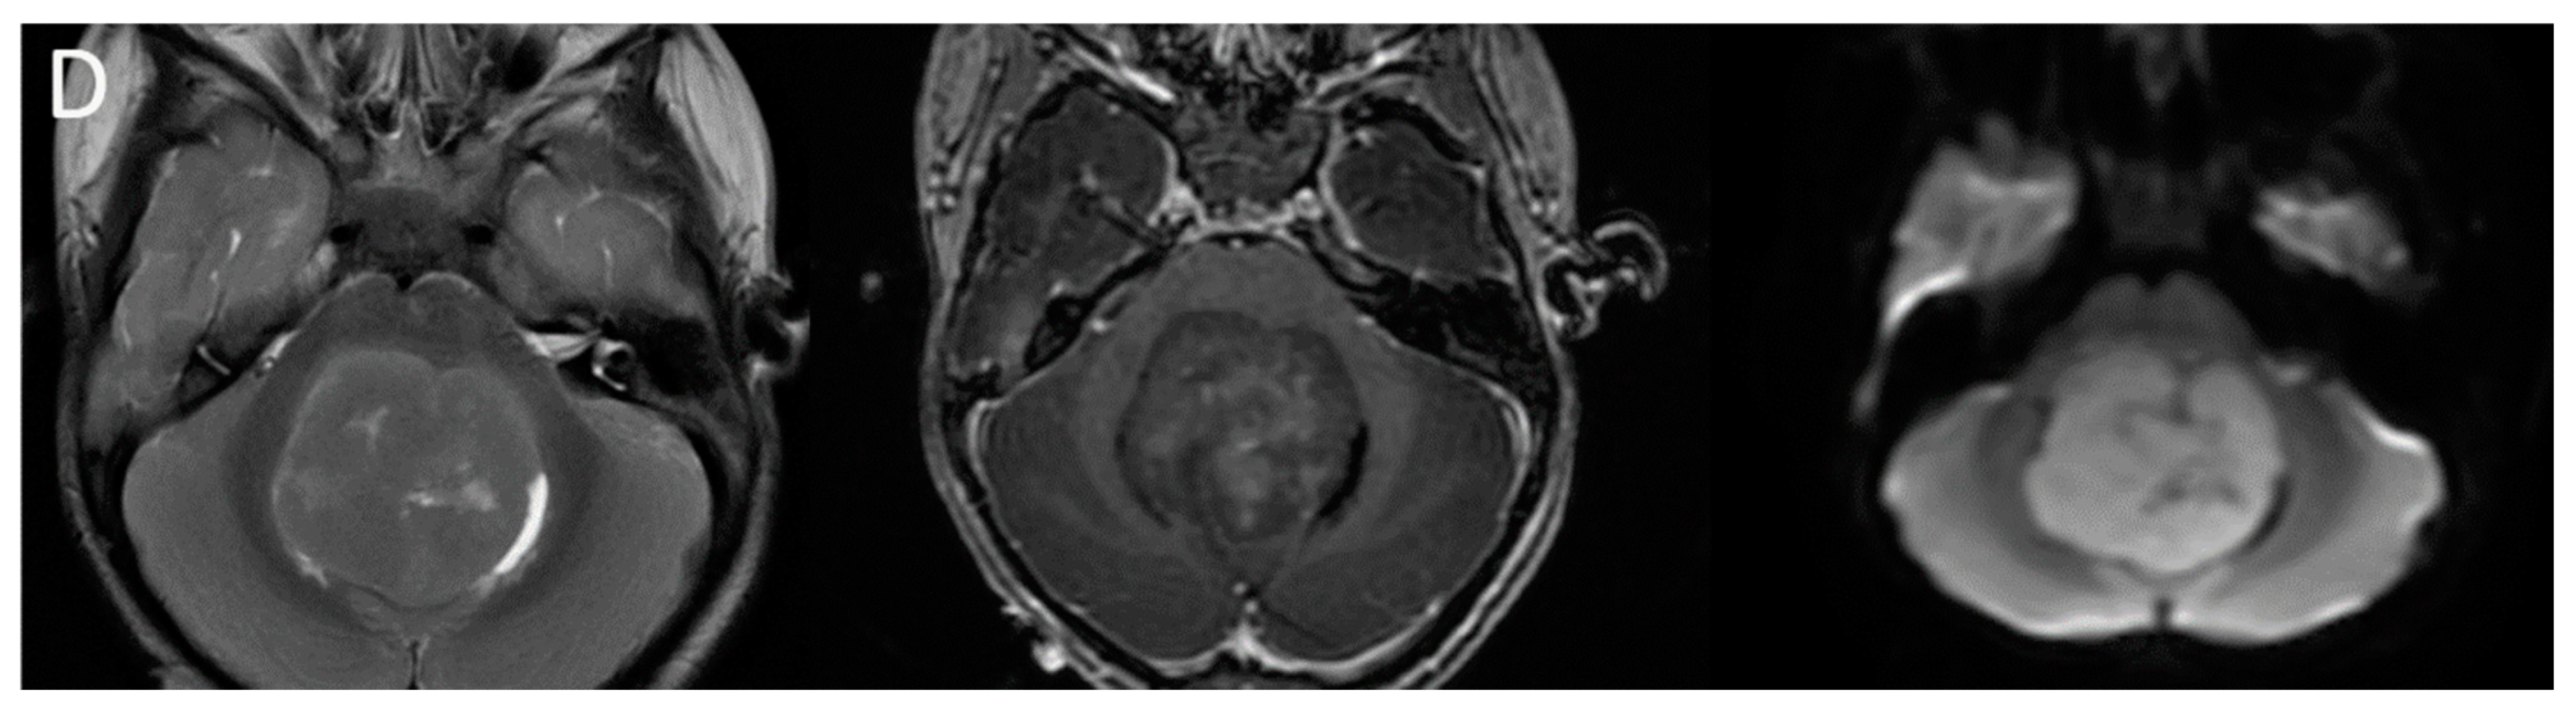

| Atypical teratoid/rhabdoid tumor | Posterior fossa (slightly more common) or cerebral hemispheres May be extra-axial | Diffusion restricting Enhancement usually present More heterogenous than medulloblastomas, with cysts/necrosis, calcification, and hemorrhage |